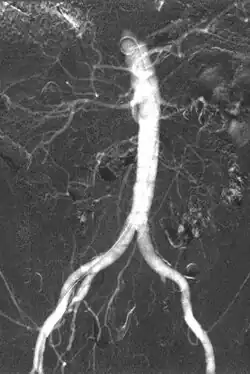

Iodinated contrast contains iodine. It is the main type of radiocontrast used for intravenous administration. Iodine has a particular advantage as a contrast agent for radiography because its innermost electron ("k-shell") binding energy is 33.2 keV, similar to the average energy of x-rays used in diagnostic radiography. When the incident x-ray energy is closer to the k-edge of the atom it encounters, photoelectric absorption is more likely to occur. Its uses include:

- Angiography (arterial investigations)

- Venography (venous investigations)